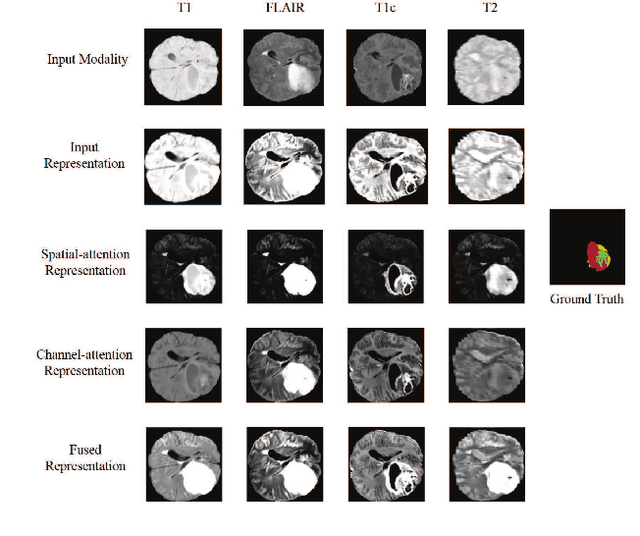

Abstract:In the field of multimodal segmentation, the correlation between different modalities can be considered for improving the segmentation results. Considering the correlation between different MR modalities, in this paper, we propose a multi-modality segmentation network guided by a novel tri-attention fusion. Our network includes N model-independent encoding paths with N image sources, a tri-attention fusion block, a dual-attention fusion block, and a decoding path. The model independent encoding paths can capture modality-specific features from the N modalities. Considering that not all the features extracted from the encoders are useful for segmentation, we propose to use dual attention based fusion to re-weight the features along the modality and space paths, which can suppress less informative features and emphasize the useful ones for each modality at different positions. Since there exists a strong correlation between different modalities, based on the dual attention fusion block, we propose a correlation attention module to form the tri-attention fusion block. In the correlation attention module, a correlation description block is first used to learn the correlation between modalities and then a constraint based on the correlation is used to guide the network to learn the latent correlated features which are more relevant for segmentation. Finally, the obtained fused feature representation is projected by the decoder to obtain the segmentation results. Our experiment results tested on BraTS 2018 dataset for brain tumor segmentation demonstrate the effectiveness of our proposed method.

Abstract:In the field of multimodal segmentation, the correlation between different modalities can be considered for improving the segmentation results. In this paper, we propose a multi-modality segmentation network with a correlation constraint. Our network includes N model-independent encoding paths with N image sources, a correlation constraint block, a feature fusion block, and a decoding path. The model independent encoding path can capture modality-specific features from the N modalities. Since there exists a strong correlation between different modalities, we first propose a linear correlation block to learn the correlation between modalities, then a loss function is used to guide the network to learn the correlated features based on the linear correlation block. This block forces the network to learn the latent correlated features which are more relevant for segmentation. Considering that not all the features extracted from the encoders are useful for segmentation, we propose to use dual attention based fusion block to recalibrate the features along the modality and spatial paths, which can suppress less informative features and emphasize the useful ones. The fused feature representation is finally projected by the decoder to obtain the segmentation result. Our experiment results tested on BraTS-2018 dataset for brain tumor segmentation demonstrate the effectiveness of our proposed method.